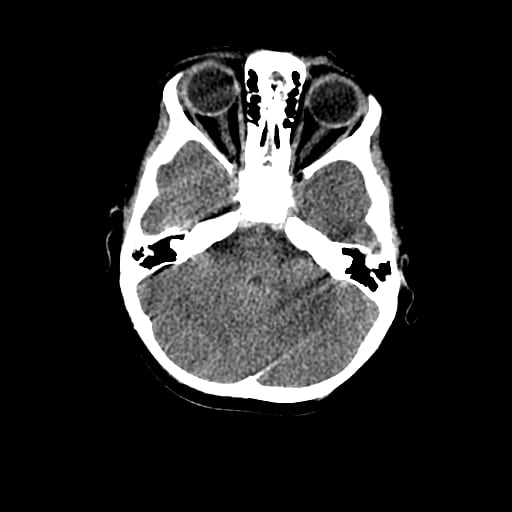

Age: 1

Sex: Male

Indication: Fall